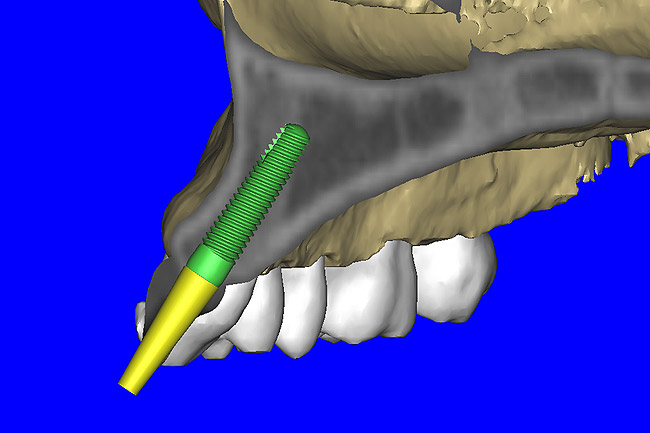

After the basic plan had been established, it was re-evaluated using interactive 3D images. The reconstructed 3D view of the maxilla clearly illustrated the extent of the bilateral facial concavities, and the root eminences of the adjacent and posterior teeth (Figure 7A). The placement of the virtual implants then was evaluated to ensure that the facial cortical plate was not perforated (Figure 7B). The implants were labeled individually as “7” and “10,” with the simulated yellow abutment projection indicating the facial-lingual inclination through the bone to the level above the incisal edge of adjacent teeth. The ability to gain a better understanding of these individual root forms can not be underestimated. The dental literature has suggested certain parameters for placing implants near teeth and implants next to other implants. However, there is little scientific 3D documentation to support these suggested rules.5-10 The use of an interactive treatment-planning software application permits closer scrutiny of previously difficult-to-visualize areas, and can now be used to redefine perceptions of spatial positioning of implants, especially when in close proximity to natural tooth roots, vital anatomy, and adjacent implants.27-29

Using different masking (segmentation) and threshold Hounsfield unit values, several new 3D bone volumes can be created which offer invaluable information. To help determine the final position of each implant a new bone model was created with a Hounsfield unit value of 1480, which eliminated all but the densest objects included in the scan data. (Results may vary depending on the CBCT machine used.) The inner and outer layers of bone were removed, leaving the underlying enamel and root structure of the teeth (Figure 8A). After the bone had been stripped away, the root inclinations were examined closely. The most striking findings confirmed the rotated position of the right central, while revealing the slight mesial dilaceration of the root apex, which converged on the space needed for the path of the potential implant (Figure 8B). The schematic shapes of the proposed implants were visualized for the right and left lateral spaces in different rotations of the 3D maxillary arch. It was at this point that a determination was made as to the appropriate implant shape and type that would fit the available space while avoiding encroachment on adjacent tooth roots. A tapered design implant (Tapered Screw-Vent®, Zimmer Dental, www.zimmerdental.com) was chosen from the large virtual library. With the SIMPlant software, the virtual library contains data from dozens of implant manufacturers and realistic.computer-aided design representations as seen in Figure 9A through the translucent bone. The position of the left implant can be visualized with adequate mesial-distal distance between adjacent tooth roots (Figure 9B) and a more delicate placement (Figure 9C).

Figure 7a  The 3D reconstruction showed (A) the facial concavities and root eminences, and allowed (B) for evaluation of virtual implant placement to ensure the facial cortical plate was not perforated.

Figure 7a

Figure 7b  The 3D reconstruction showed (A) the facial concavities and root eminences, and allowed (B) for evaluation of virtual implant placement to ensure the facial cortical plate was not perforated.

Figure 7b